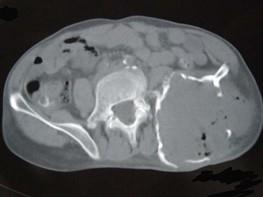

问题 患者,女性,68岁,近2年来感左髋部疼痛,活动后加重,2周前由于剧烈运动后左下肢活动不能,查体左髋部压痛明显,皮肤稍显红肿,请结合所提供的图像,选择最佳选项 ( )

选项 A、转移瘤 B、软骨肉瘤 C、骨巨细胞瘤 D、动脉瘤样骨囊肿 E、骨囊肿

答案 D